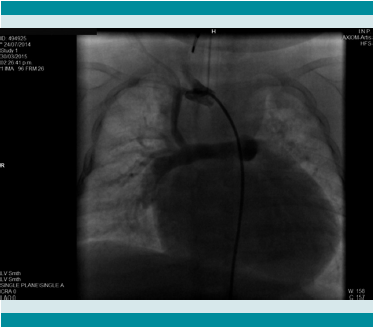

El paciente presentaba edema generalizado, piel fría y marmórea, pupilas midriáticas no reactivas, acrocianosis con llenado capilar de 8 segundos. En virtud de la aparente oclusión de la fístula sistémico pulmonar y la comunicación interatrial restrictiva, pasó a estudio hemodinámico con la intención de hacer una septostomía de Rashkind. En el cateterismo se comprobó la fístula permeable con estenosis leve a moderada en el origen de la subclavia derecha. Durante el cateterismo presentó bradicardia y paro cardiaco; las maniobras de reanimación durante 30 minutos no lograron revertirlo y el paciente falleció.

Se realizó cateterismo cardíaco a solicitud del Servicio de Cardiología por incremento de la cianosis, con desaturación significativa y el hallazgo del segundo estudio ecocardiográfico, donde al parecer había sospecha de obstrucción al flujo sanguíneo de la fístula sistémico-pulmonar. El estudio hemodinámico evidenció que la fístula se encontraba permeable, sin datos de obstrucción con flujo adecuado hacia ambas ramas pulmonares (Figura 2).